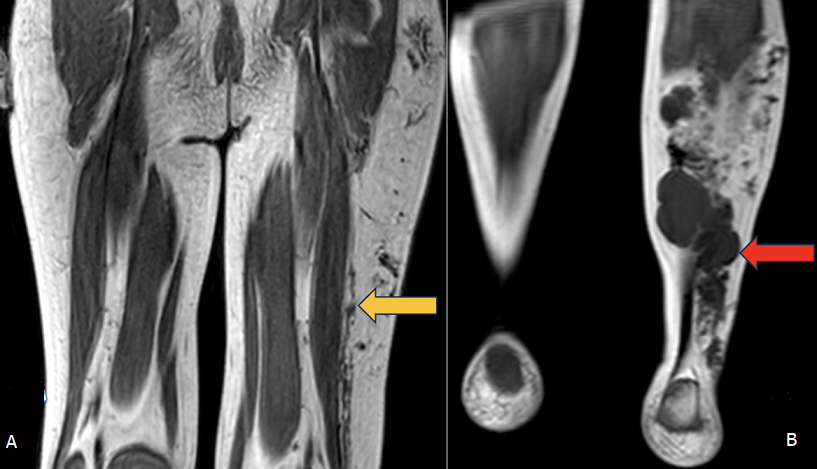

Extensive slow-flow vascular malformation of the left lower limb

A 5-year-old boy presented with progressive swelling and hypertrophy of the left lower limb since early childhood. The swelling was painless and gradually increased in size, with no history of trauma or systemic symptoms. Magnetic resonance imaging (MRI) angiography of the left lower limb was performed using spiral axial sections with coronal and sagittal reformatted images. MRI revealed diffuse T1 hypointense lesions extending across the fascial planes of the left thigh, knee, and leg involving both medial and lateral compartments (B). The entire left limb appeared hypertrophied (A), and multiple lobulated lesions were noted in the calf region, the largest measuring approximately 3.8x2.9cm. Scattered T1 hypointense foci, likely phleboliths, were observed within the lesions. The underlying bones, including the femur, tibia, fibula and ankle joints, demonstrated normal signal intensity with no evidence of marrow involvement or abnormal vascular flow voids. Vascular malformations are congenital anomalies of vascular development, classified based on their flow characteristics into slow-flow (venous, lymphatic or capillary) and high-flow (arteriovenous) lesions. Venous malformations are the most common type of slow-flow lesions, typically presenting as soft, compressible and non-pulsatile masses that may cause limb hypertrophy and contain phleboliths. MRI plays a crucial role in assessing the lesion´s extent, tissue involvement and hemodynamic pattern. In this case, imaging findings of diffuse T1 hypointense lesions with phleboliths and soft tissue hypertrophy were consistent with a slow-flow venous malformation involving the thigh and leg. Early recognition using MRI is crucial for accurate classification, multidisciplinary management planning and prevention of long-term complications such as chronic pain, bleeding or limb deformity.